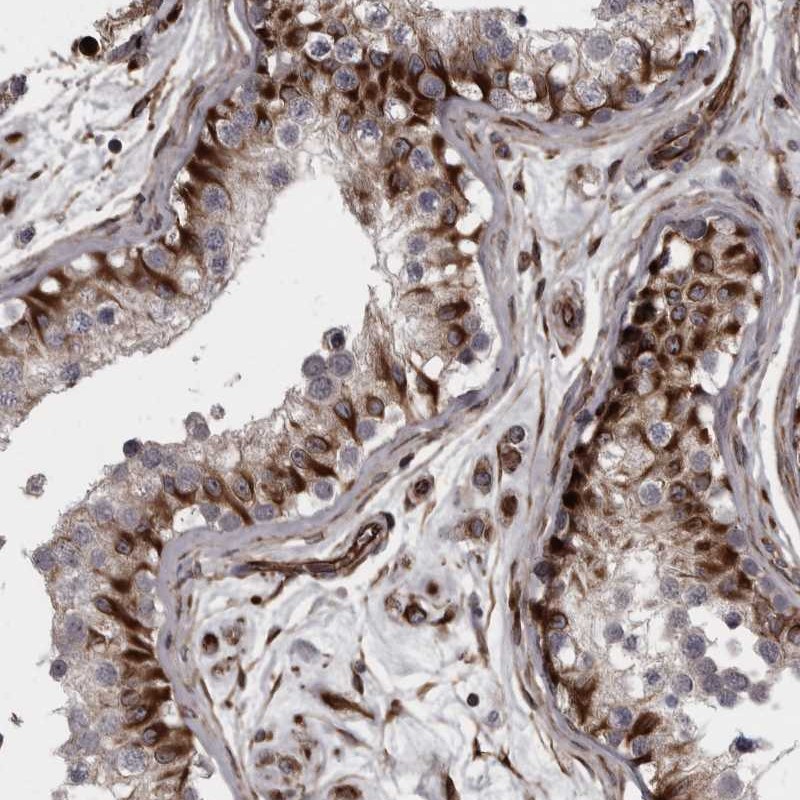

Immunohistochemical staining of human testis shows strong cytoplasmic positivity in cells of seminiferous ducts.